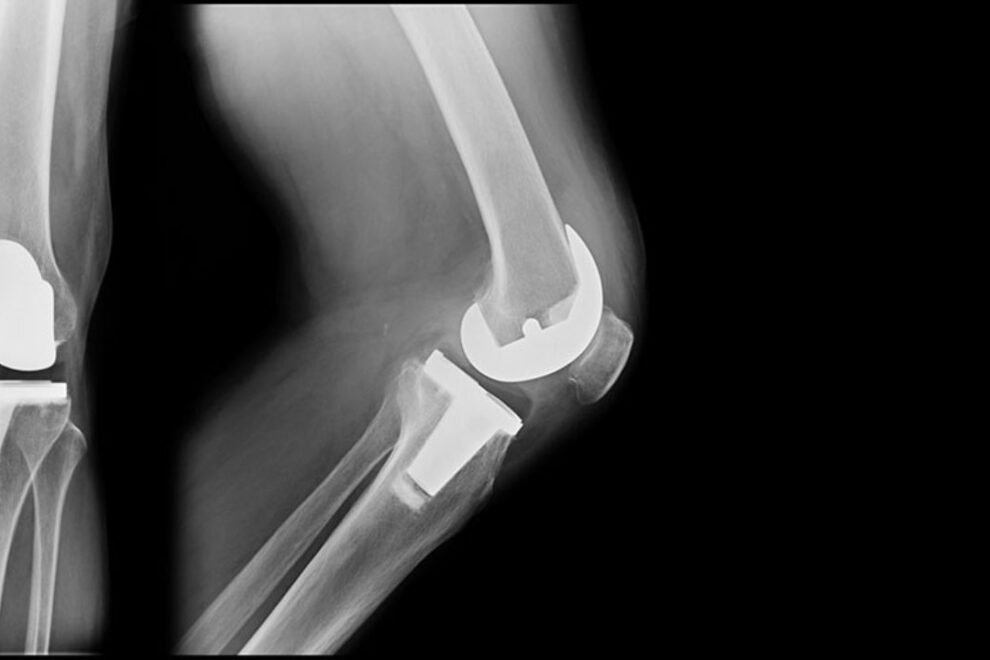

Bilateral Knee Replacement surgery is a double knee replacement surgery or knee arthroplasty, a surgical procedure in which both knee joints are resurfaced with prosthesis. A prosthesis is an artificial knee which is made up of plastic, metal, or ceramic.

In India, in Bilateral Knee Replacement surgery involves the surgical procedure for replacing both knee with the artificial implants. These are usually have the same process but there is slight difference with the surgical techniques for both the types.

The Prosthesis which implants in your knee joint section, an artificial one is designed in such manner that it can lasts upto 15-20 years of time period. It gives a long-term durability factor, its durability depends upon the age, implant material and your activity level.